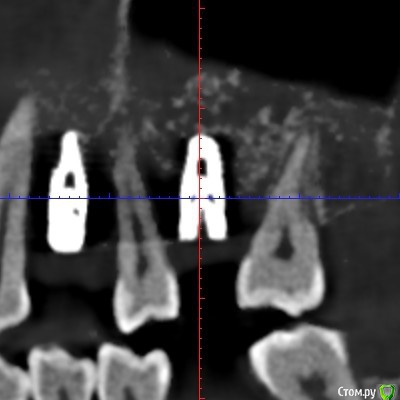

Делалась установка имплантов 5-6 месяцев назад. Скоро буду установлены формирователи десны, а потом временные коронки, с которыми ходить полгода. Для того, чтобы за это время свести к минимуму последующее обтачивание своих здоровых зубов при постановке постоянных коронок на импланты, ортопед отправил на консультацию к ортодонту, сказав, что можно попытаться если не полностью, то хотя бы с каким-то эффектом переместить сместившиеся зубы. Хирург в некотором роде поддержал, сказав, что использование временных коронок в качестве опоры для перемещения даст нагрузку на импланты и будет даже положительным фактором, если нагрузка не будет слишком большая.

Одна отнеслась к описанной ситуации совершенно спокойно, согласилась, что слишком большую нагрузку давать не надо, а потихоньку можно вполне успешно закрепить ортодонтическую конструкцию на временных коронках 24 и 26 для перемещения с помощью пружин зуба 25 к 24, а зуба 27 - от 26, туда, где они и были не так давно, перед имплантацией. По времени спрогнозировала порядка 3-4 месяцев. В отношении зуба 37 с отталкиванием от временной коронки на 36 тоже никаких возражений не было, только по времени могло быть немного дольше, так как кость плотнее.

Вторая категорически отвергла укрепление дуг брекетов на 24 и 26. Мотивировала это низкой плотностью кости на этом участке, при которой пострадают импланты. Сказала, что если перемещать конкретно два зуба 25 и 27, то она прикрепит конструкцию только к ним, и они будут отталкиваться друг от друга без участия временных коронок. Прогноз по сроку увеличился от 6 до 12 месяцев, причём ещё была озвучена вероятность выталкивания зуба 25 при перемещении в наружную сторону. По зубу 37 опора на временную коронку на импланте также была отвергнута и предложен вариант с перемещением при помощи вкрученного мини-импланта в кость за зубом.